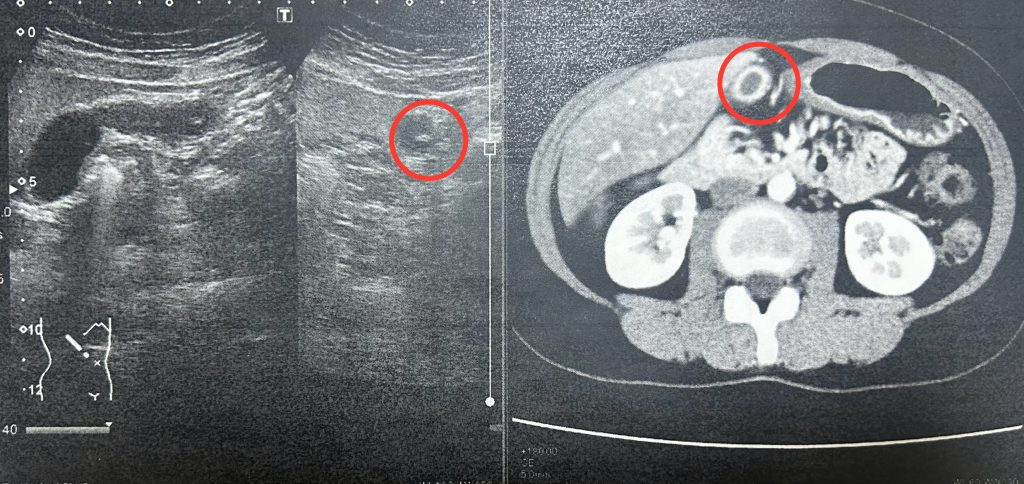

検査をして分かったこと

- 胆石が認められた

- 下の写真左の中央、白い丸が胆石です。

- 胆のうが全体的に炎症状態

- 下の写真右の白くなっている箇所が炎症部位だそうです

- 白血球の数値が上がっている

- 胆のうのくびれが強く、2つ部屋があるような状態になっている(先天的)

- 胆のうが通常とは逆側についている(先天的)

あらかた予想通りではありましたが、「胆のうの位置が常人とは違う」というのは衝撃でした。この段階で、手術時の事故を避けるため、念の為造影剤を使ってのCT検査も受けることになりました。